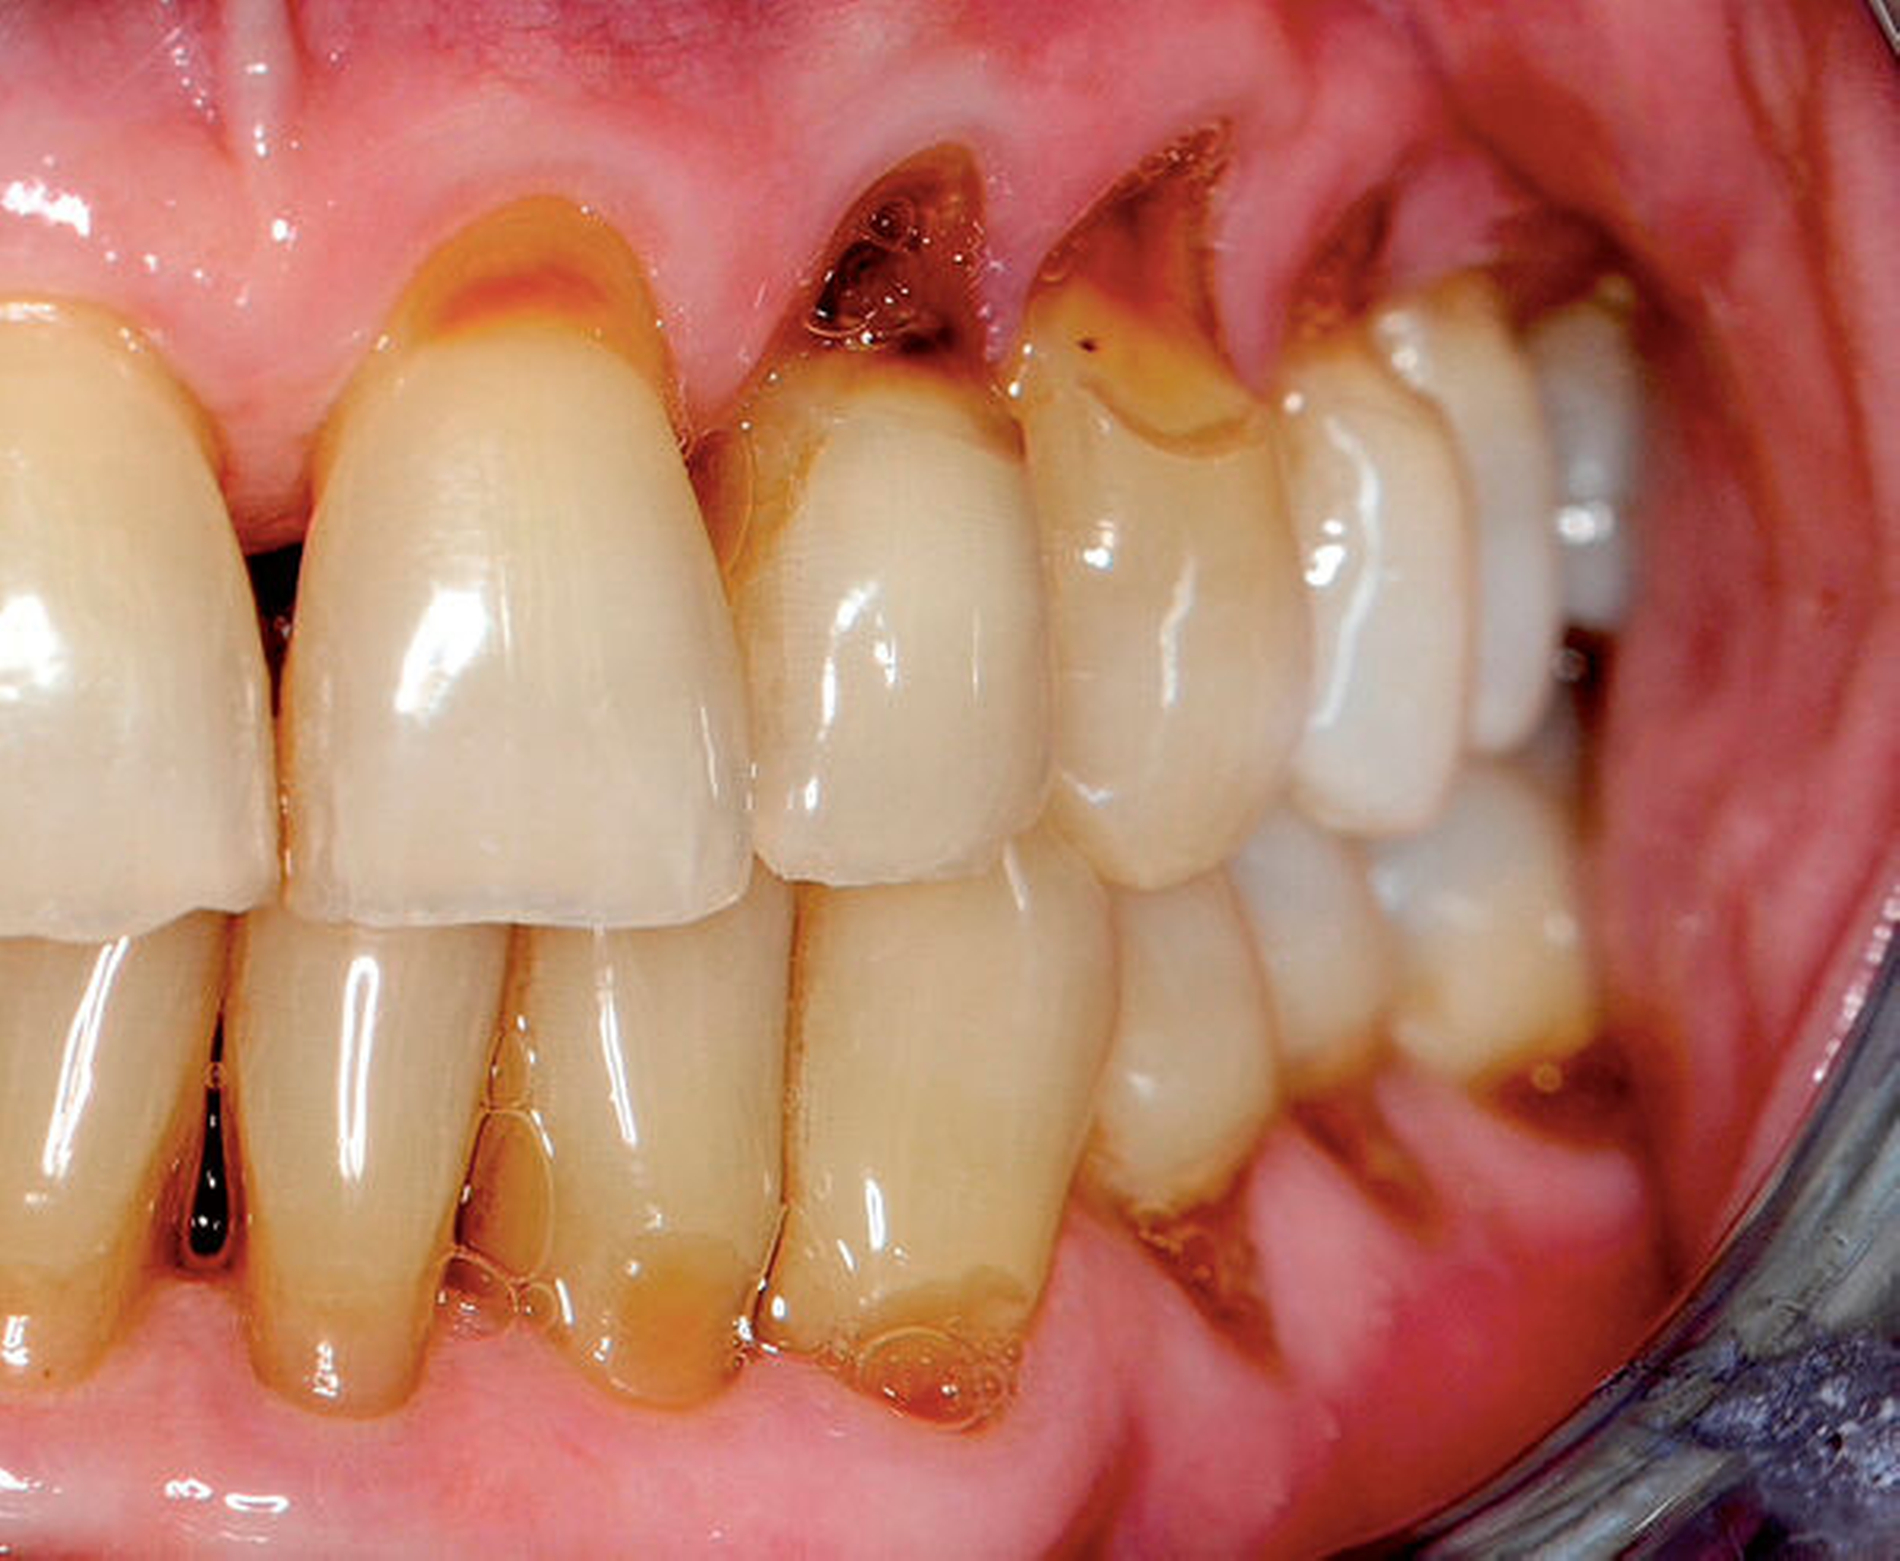

Sekundär entwickeln sich oft bakterielle, virale und mykotische Schleimhautinfektionen. Man beobachtet des Weiteren eine progrediente Zunahme kariöser Läsionen an Glattflächen, Füllungs- und Kronenrändern sowie im Bereich von Wurzeloberflächen [Jaschinski et al., 2009] (Abbildung 2a).

Beide Formen oraler Veränderungen – die mehr oder weniger stark ausgeprägten Verminderungen des Speichelflusses und die gingivalen Wucherungen – bereiten dem Zahnarzt häufig große Probleme. Als Folge der fehlenden protektiven Wirkung des Speichels können sich kariöse Läsionen – besonders im Bereich der Zahnhälse – 15-mal schneller entwickeln [Jaschinski et al., 2009]. Weiterhin können in fortgeschrittenen Fällen gingivale Wucherungen die Durchführung der Mundhygiene und die Therapie von kariösen Defekten in unmittelbarer Nähe der Gingiva erschweren. Trotz der bestehenden Schwierigkeiten sollte die vom Hausarzt, Kardiologen oder Neurologen verordnete Medikation auf keinen Fall eigenmächtig verändert oder gar abgesetzt werden. Stattdessen empfiehlt sich bei beiden Patientengruppen eine Intensivierung der Plaquekontrolle durch eine individuell abgestimmte Instruktion zur Durchführung der Mundhygiene (MHD) und in kurzen Zeitabständen durchgeführte professionelle Zahnreinigungen (Abbildung 2).